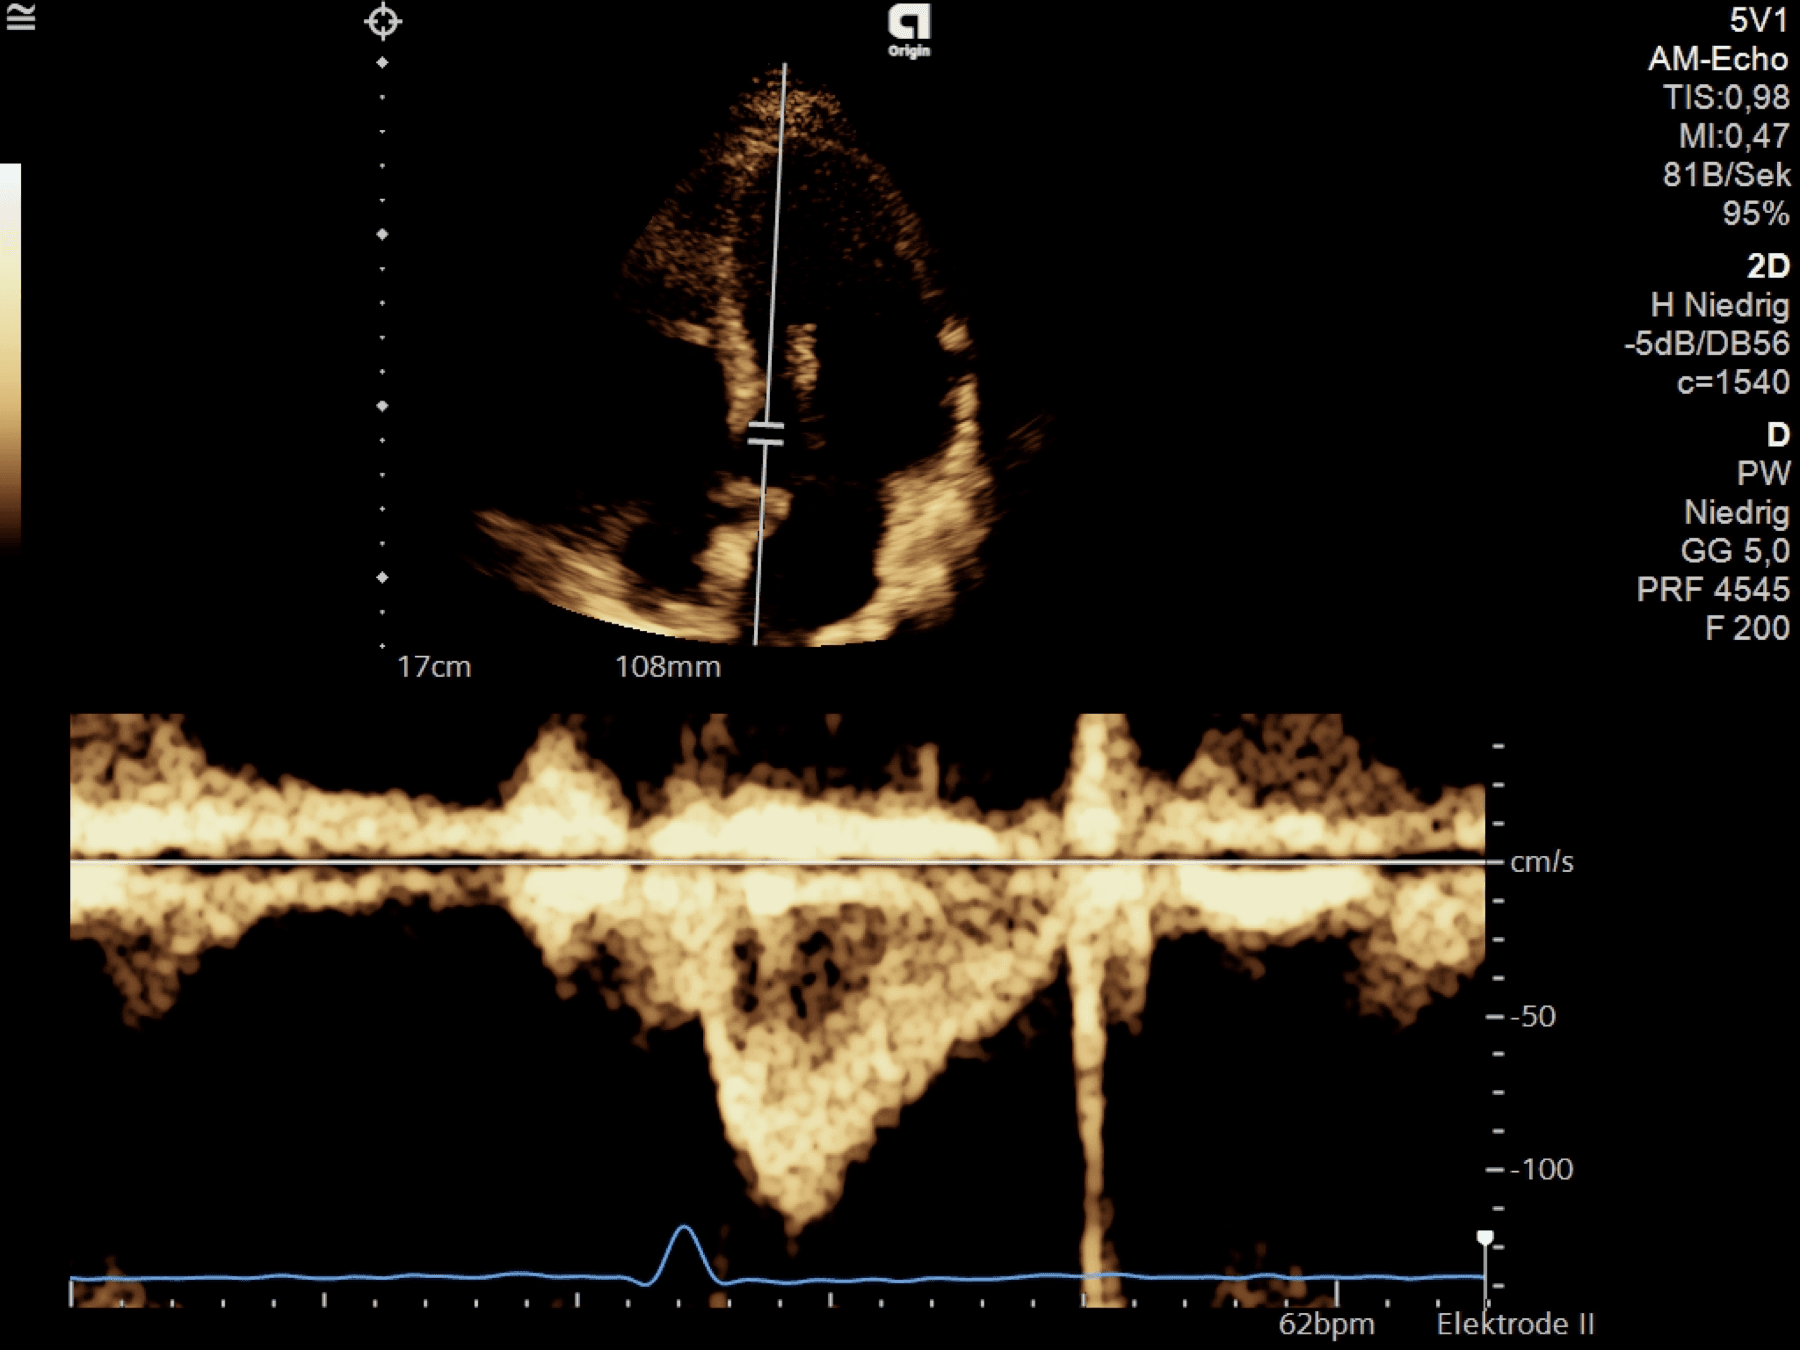

LV diastole

IVRT

AVC to MV-opening (MVO)

Isovolumic relaxation — compression & torsion lead to energy of the elastic elements of the cardiomyocytes & extracellular matrix in end-systole ➜ recoil & untwist in early diastole due to „relaxed state“ + active myocyte relaxation ➜ LV-volume ↑ & LV-pressure ↓ = measurable

At the beginning of diastole, LV pressures are just below AV pressures; the LV pressures are just above the LAP ➜ the IVRT is a short time interval of expansion of the LV without volume change ➜ AV & MV are closed = isovulmetric relaxation time (around 40ms)